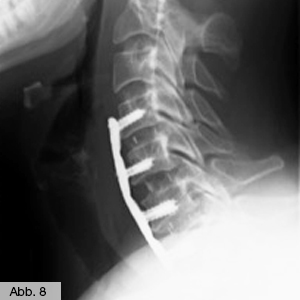

Dieser zusätzliche Knocheneinbau führt oft neben der Stabilisierung auch zu einer Einengung des Spinalkanals oder der Nervenaustrittstellen. Auch bei diesem Krankheitsbild kommen alle oben genannten, nicht-operativen Maßnahmen in unserer Klinik zur Anwendung. Bei fehlendem Erfolg wird dann geprüft, ob ein aufwendiger Eingriff mit Erweiterung des Spinalkanals, Wiederbegradigung und Stabilisierung der Wirbelsäule sinnvoll ist, welcher dann in unserer Klinik durchgeführt wird. Solche Eingriffe führen wir an der Hals-, Brust- und Lendenwirbelsäule durch (Abb. 7 & 8).

Bild Orthopädie Wirbelgleiten